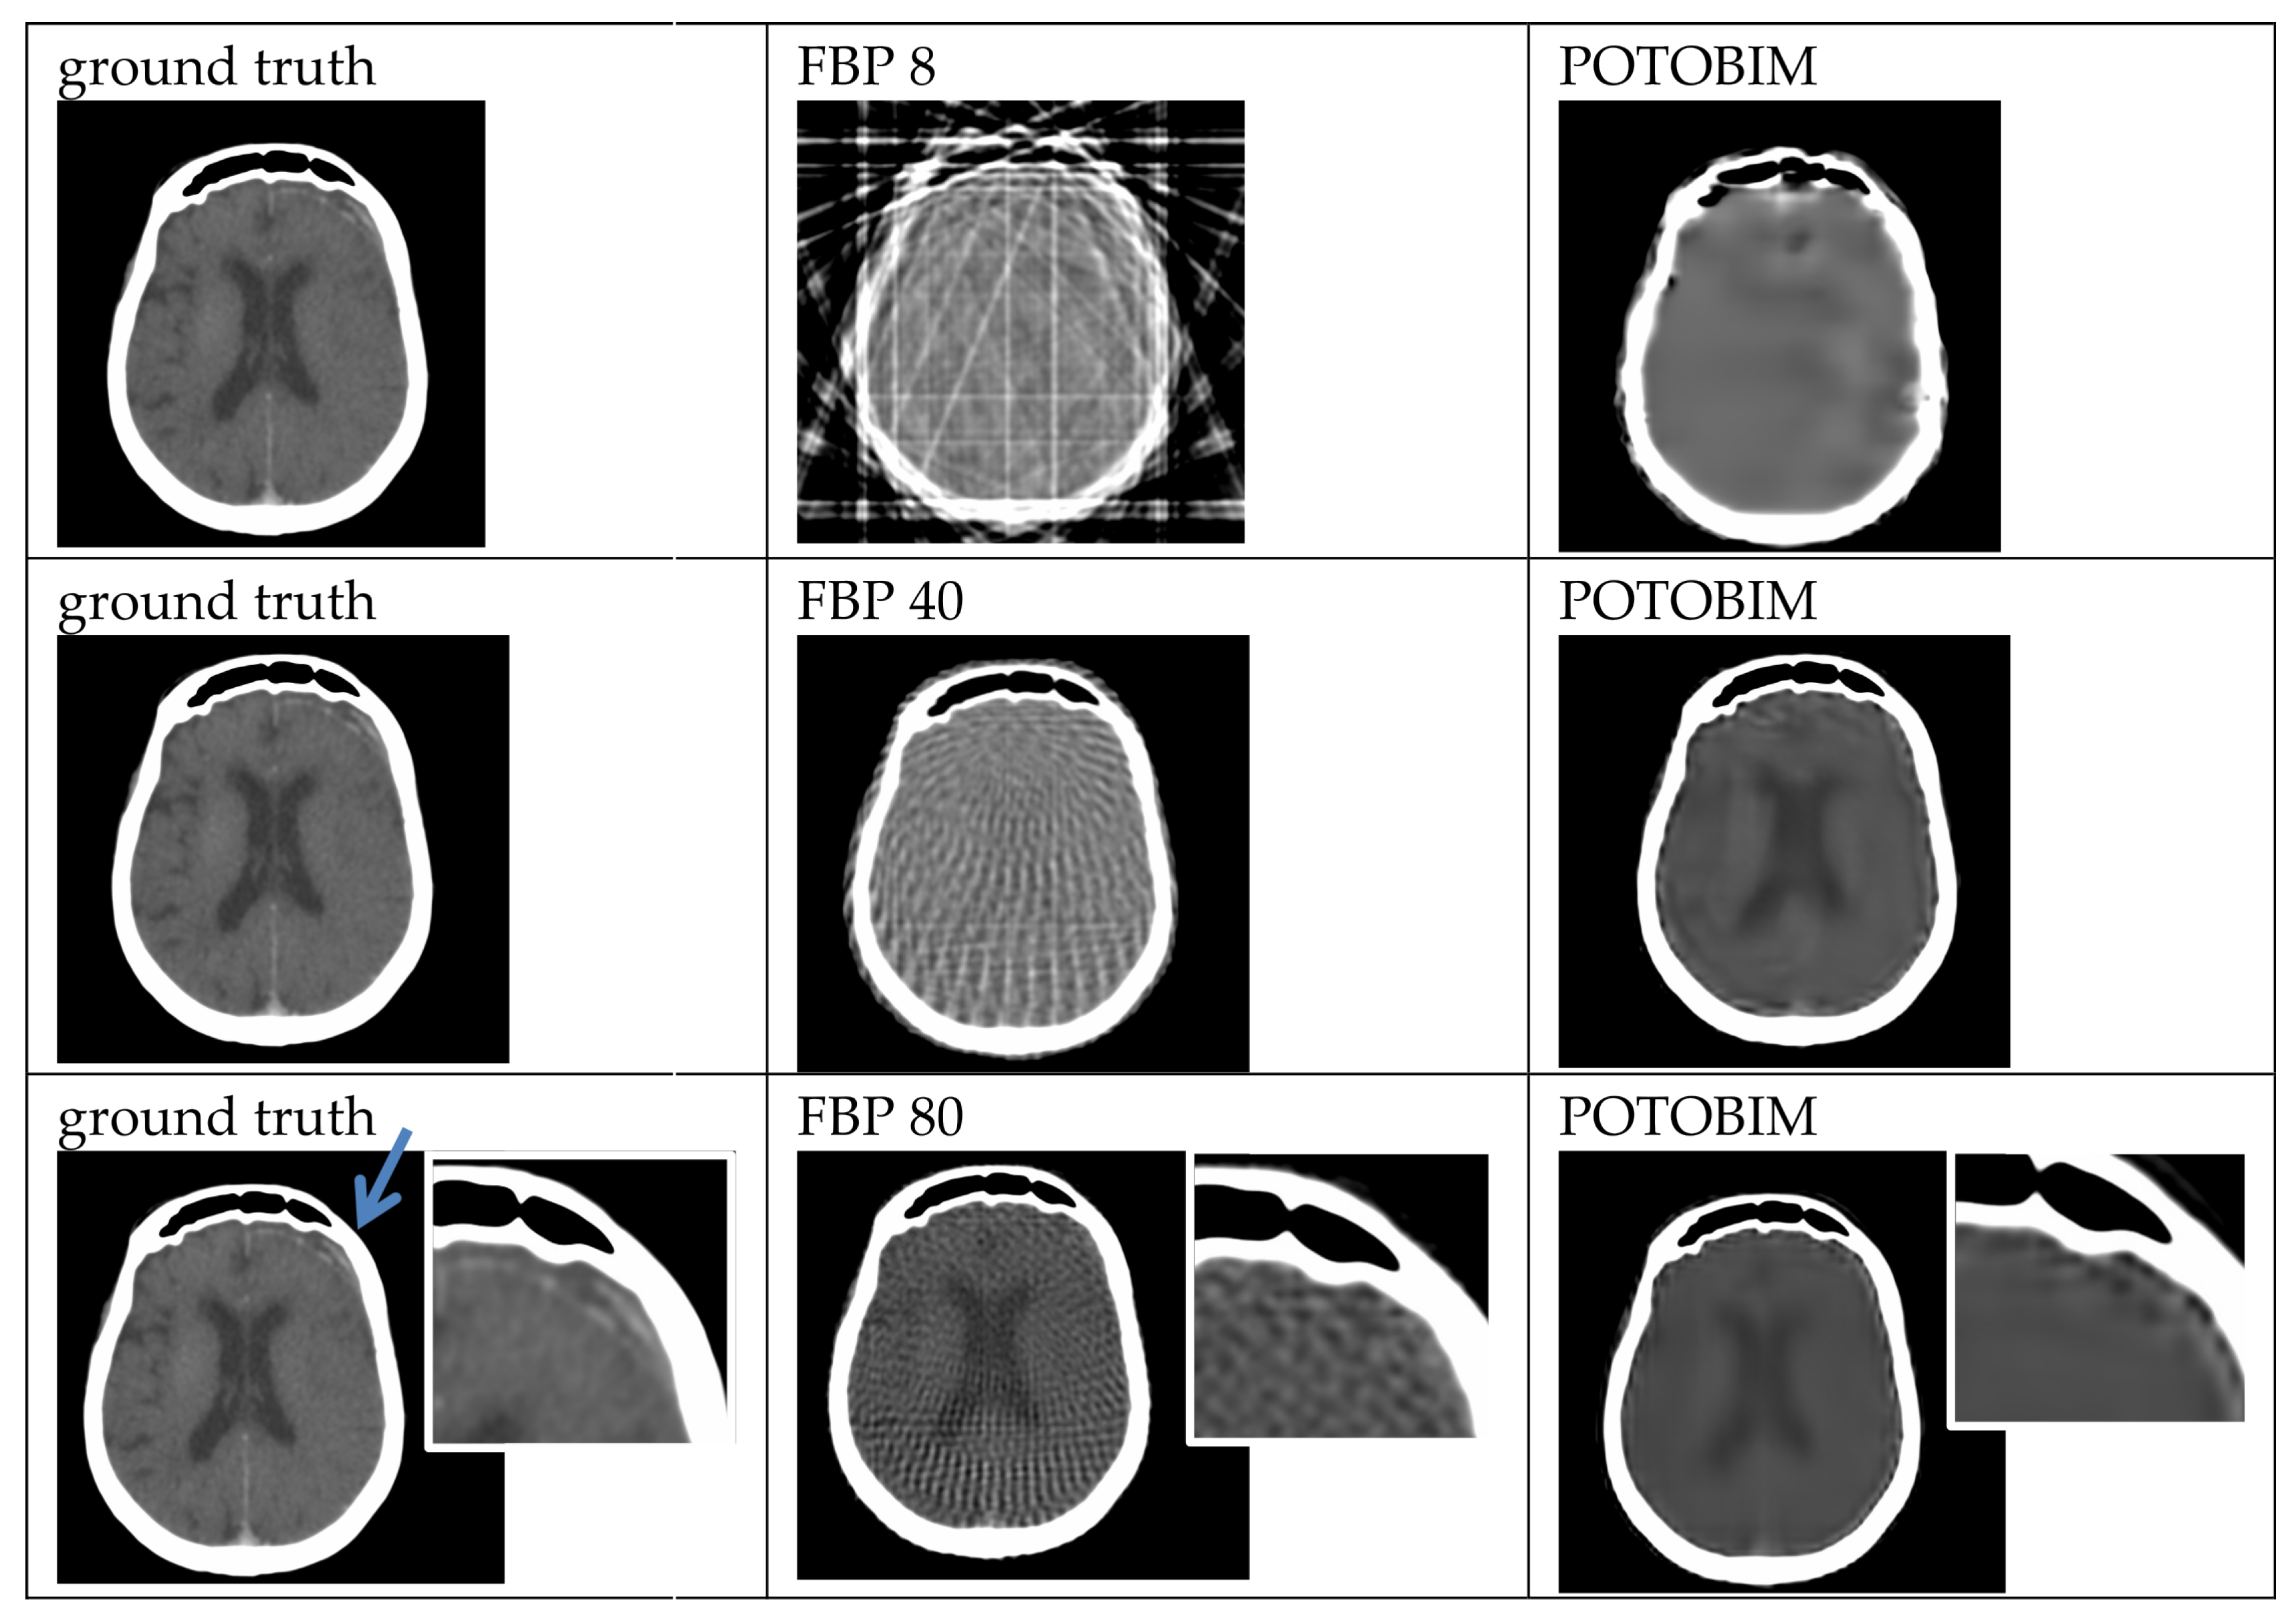

Figure A1. Exemplified images (subdural hematoma left, blue arrow) for reconstruction with 8, 40 and 80 projections used with the FBP (center) and POTOBIM (right). In comparison, the reference image using all projections (left). Detailed view (white box) displaying relevant anatomical region.